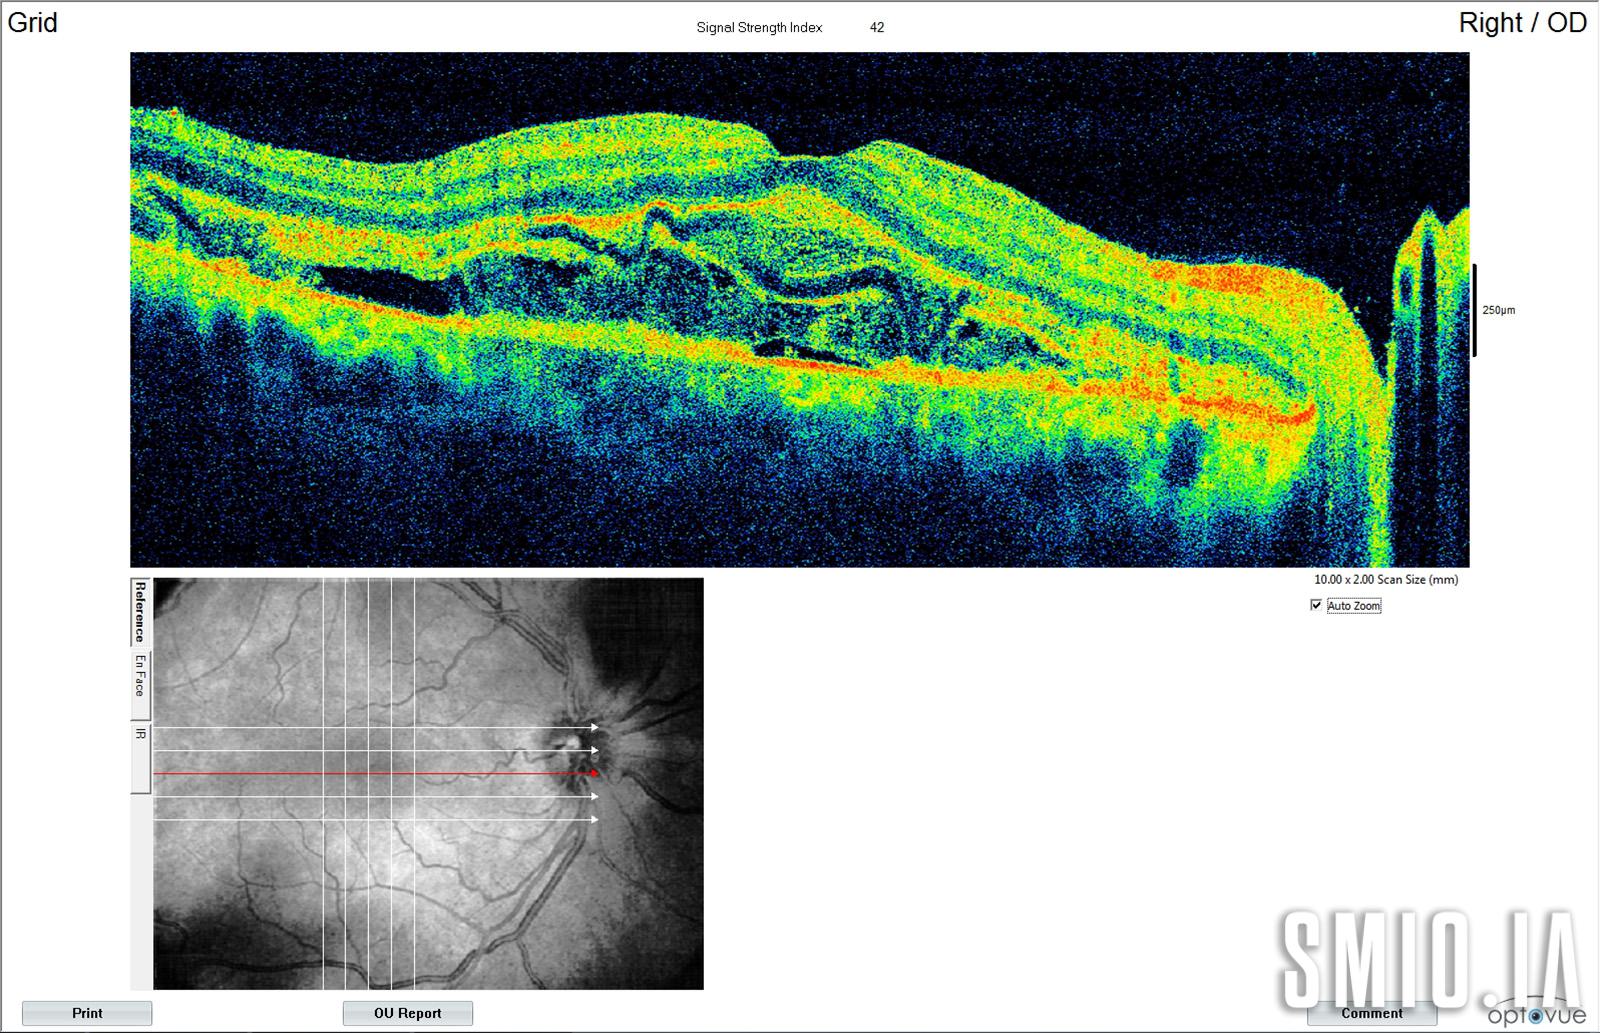

Description: La Choroï-rétinopathie hypertensive présente cliniquement avec des décollement rétinien séreux et des lésions de l'épithélium pigmentaire rétinien jaunâtre 4 jours après l'accouchement chez une femme 28 qui présente le jour de l'accouchement baisse de l'acuité visuelle bilatérale. Sa pression artérielle était de 174/97 mm Hg et l'OCT a montré un liquide sous-rétinien et rétinien avec une exsudation fibrinoïde.

Appareil d'imagerie: Zeiss Visucam 500 OCT Optovue